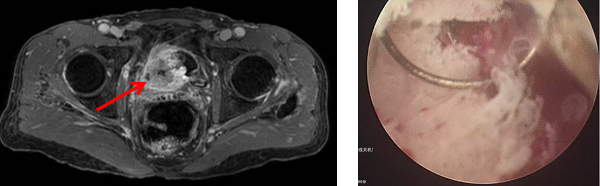

在順利完成3個(gè)周期的規(guī)范聯(lián)合治療后,2026年1月,復(fù)查的影像學(xué)檢查顯示,張先生原膀胱內(nèi)的巨大腫塊已經(jīng)基本消失,受侵犯的輸尿管管壁及周圍組織也得到修復(fù),右腎積水明顯減輕。

術(shù)后影像顯示腫瘤被切除